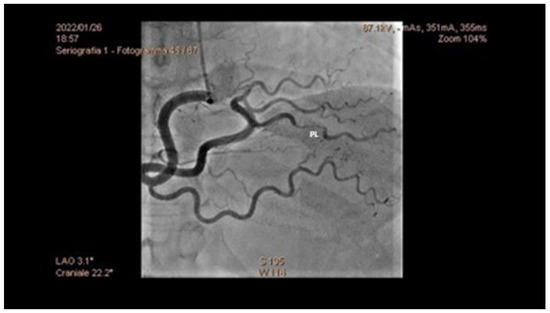

Chronic or Changeable Infarct Size after Spontaneous Coronary Artery Dissection

by Gordana Krljanac, Svetlana Apostolovic, Zlatko Mehmedbegovic, Olga Nedeljkovic-Arsenovic, Ruzica Maksimovic, Ivan Ilic, Aleksandra Djokovic, Lidija Savic, Ratko Lasica and Milika Asanin

Diagnostics 2023, 13(9), 1518; https://doi.org/10.3390/diagnostics13091518 - 23 Apr 2023

Spontaneous coronary artery dissection (SCAD) could be the cause of acute myocardial infarction (AMI) and sudden cardiac death. Clinical presentations can vary considerably, but the most common is the elevation of cardiac biomarkers associated with chest discomfort. Different pathological etiology in comparison with [...] Read more.

Spontaneous coronary artery dissection (SCAD) could be the cause of acute myocardial infarction (AMI) and sudden cardiac death. Clinical presentations can vary considerably, but the most common is the elevation of cardiac biomarkers associated with chest discomfort. Different pathological etiology in comparison with Type 1 AMI is the underlying infarct size in this population. A 42-year-old previously healthy woman presented with SCAD. Detailed diagnostical processing and treatment which were performed could not prevent myocardial injury. The catheterization laboratory was the initial place for the establishment of a diagnosis and proper management. The management process can be very fast and sometimes additional imaging methods are necessary. Finding predictors of SCAD recurrence is challenging, as well as predictors of the resulting infarct scar size. Patients with recurrent clinical symptoms of chest pain, ST elevation, and complication represent a special group of interest. Therapeutic approaches for SCAD range from the ”watch and wait” method to complete revascularization with the implantation of one or more stents or aortocoronary bypass grafting. The infarct size could be balanced through the correct therapeutical approach, and, proper multimodality imaging would be helpful in the assessment of infarct size. Full article